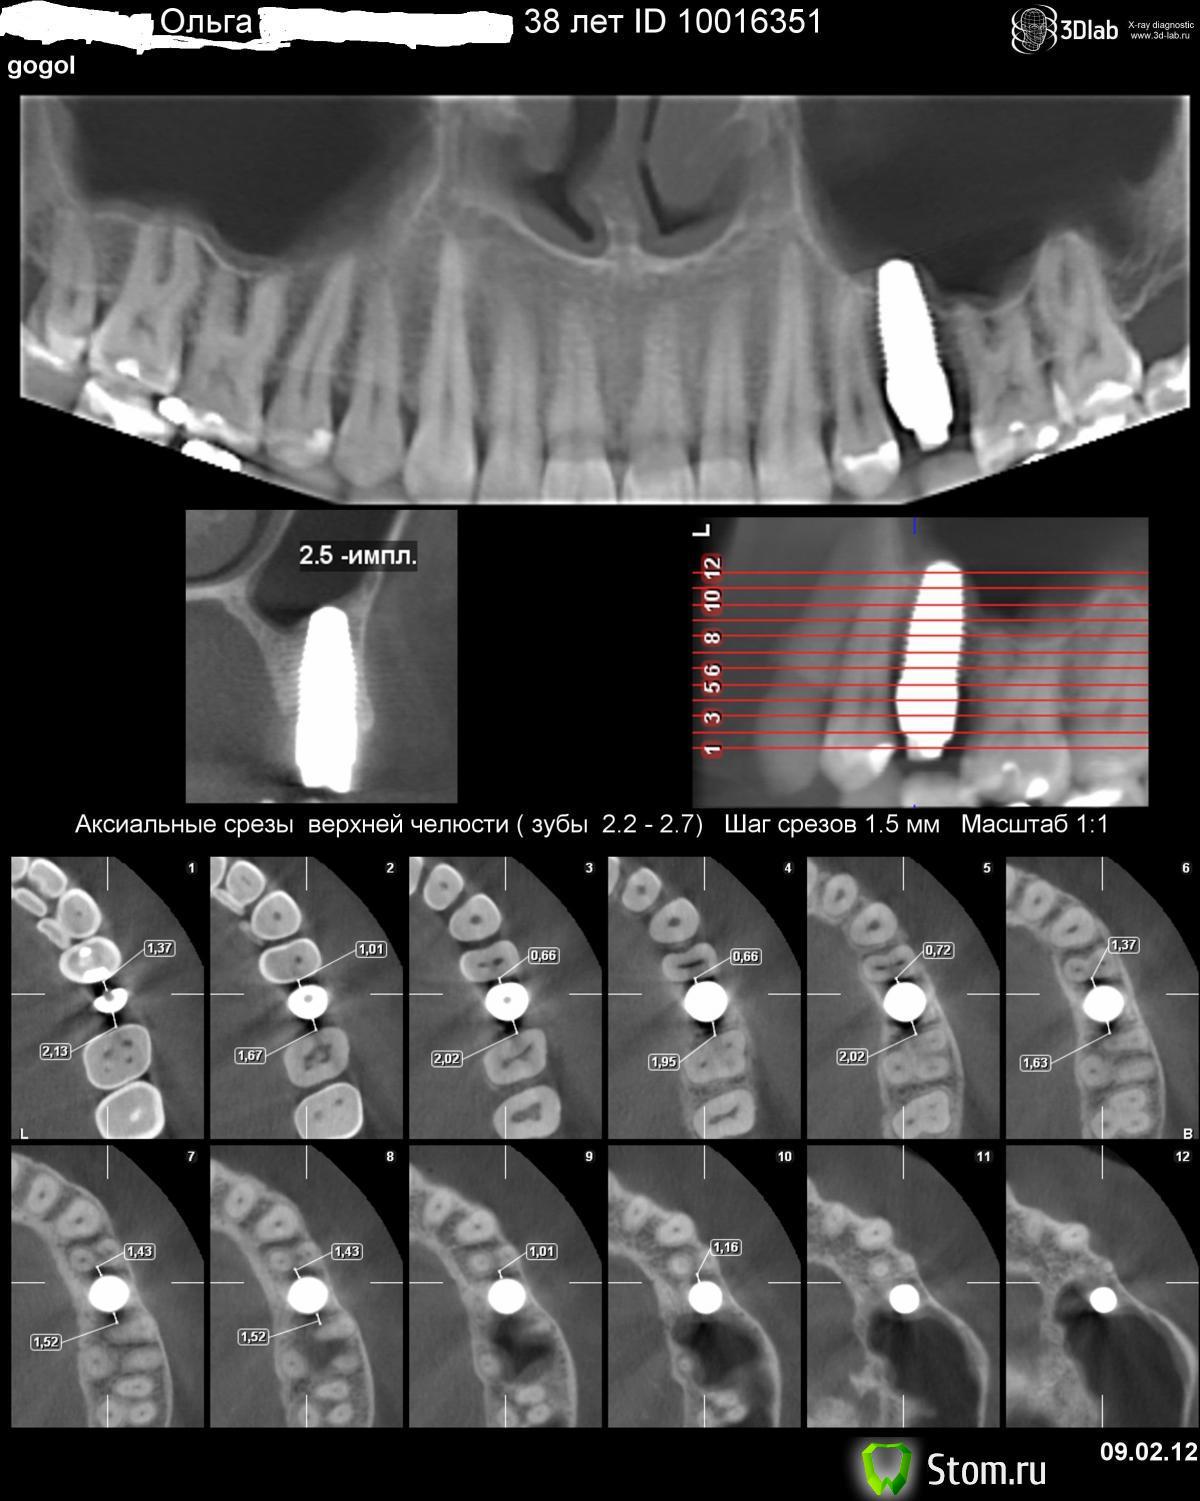

Olga Pan Опубликовано 29 апреля, 2012 Поделиться Опубликовано 29 апреля, 2012 Дорогие пациенты и стомотологи!Не знаю как мне обратиться и к кому!у меня очень серьезная дипрессия из-за громадного импланта типа Nobel Direct одномоментновместо 25-го зуба.ВСЕ БОЛИТ УЖЕ ПЯТЬ МЕСЯЦЕВ ВОКРУГ ЭТО ГВОЗДЯ-МНОГИЕ ГОВОРЯТ ПОДОЖДИ-ПОДОЖДИСКОЛЬКО ЖДАТЬ?Может кто-нибудь подскажет что делать-как жить?прикладываю 3Dlab.ПОМОГИТЕ!!! ОЛЬГА Ссылка на комментарий